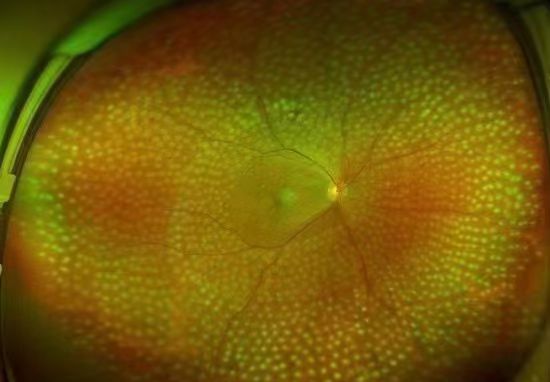

视网膜激光光凝:采用激光的热凝效用,在局部出血部位和(或)无灌注区形成凝固激光斑,达到止血、预防再出血的效果。该治疗为增殖期病变的首选治疗方式,较早实行全视网膜光凝能有效预防失明,且价格低廉,效果较好。

激光光凝治疗

眼底打激光是怎么回事?什么时候打激光?眼底激光治疗会不会引起失明?

视网膜激光光凝术是治疗糖尿病性视网膜病变(DR)的重要手段,分为全视网膜激光光凝(PRP)、黄斑格栅样激光光凝等。激光光凝术是高危增殖性糖尿病性视网膜病变(DR)患者及某些严重非增殖性患者的主要治疗方式。

激光治疗旨在减少视力进一步下降的危险,尽量保护视功能。高危增殖性糖尿病性视网膜病变患者应迅速施行全视网膜激光光凝治疗。约50%的重度非增殖性糖尿病性视网膜病变患者在1年内可进展为增殖性糖尿病性视网膜病,15%进展为高危增殖性糖尿病性视网膜病,若病情进展应考虑行全视网膜激光光凝治疗。

在激光之前,若已经出现明显的黄斑水肿,应先治疗黄斑水肿,因大面积的视网膜光凝,会导致黄斑水肿的进一步加重。以前,临床通常采用口服药物或者先对黄斑进行光凝的处理,近年来,更多采用抑制血管内皮生长因子的方法处理黄斑水肿问题。

全视网膜激光光凝术后

在结束激光治疗时,很多患者会表示视力反而不如治疗前。这种现象,实际是激光过程中,对视网膜产生了弥漫性的光漂白作用,通常半小时左右的时间就可以恢复,不需要特殊处理。总体来说,激光治疗是安全且并不会导致失明的。